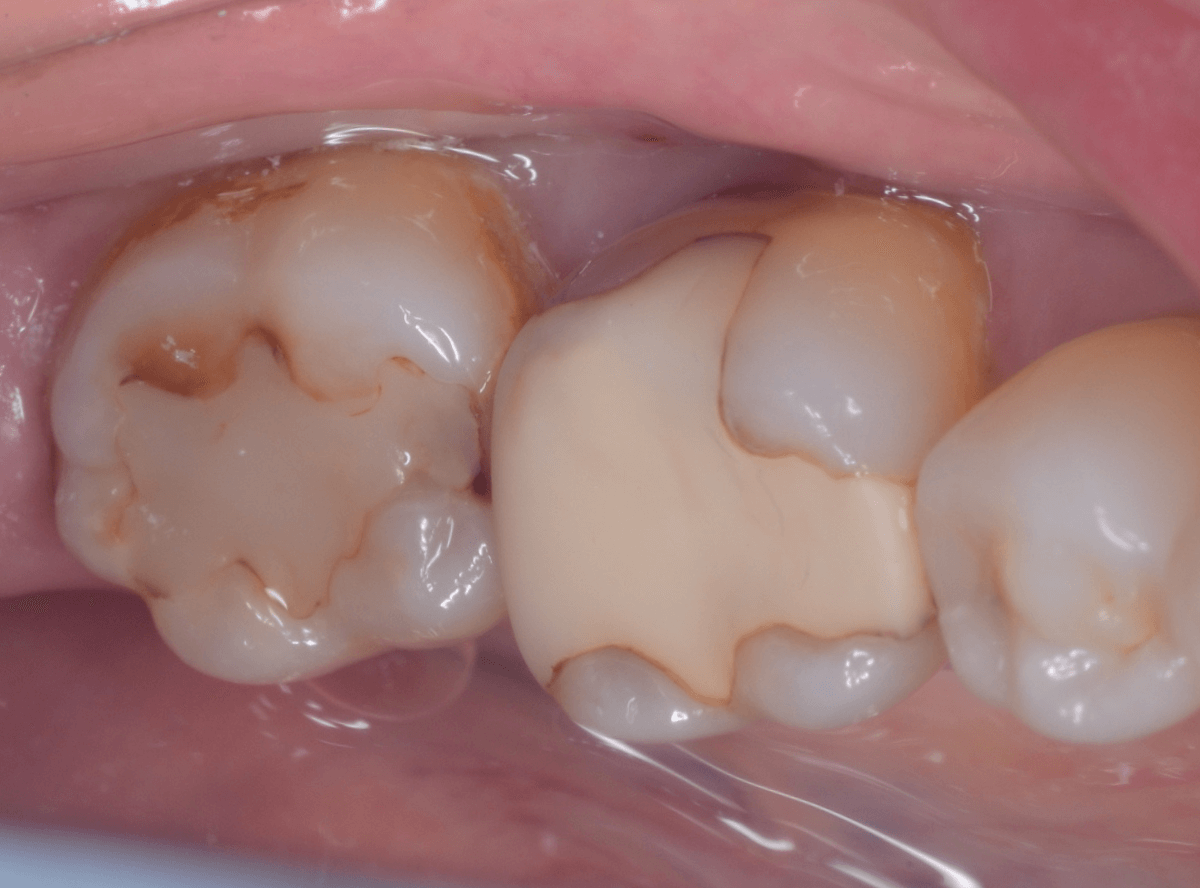

下の奥歯が虫歯になった患者さんのケースです。

〇部が虫歯の部分です。

写真で見てわかるように、常に舌が歯に触っているような状況です。

このような場合、虫歯を見つけづらいですし、治療の難易度もあがります。

虫歯の治療を開始します。

隣の歯とのすき間を中心に広い虫歯になっていました。